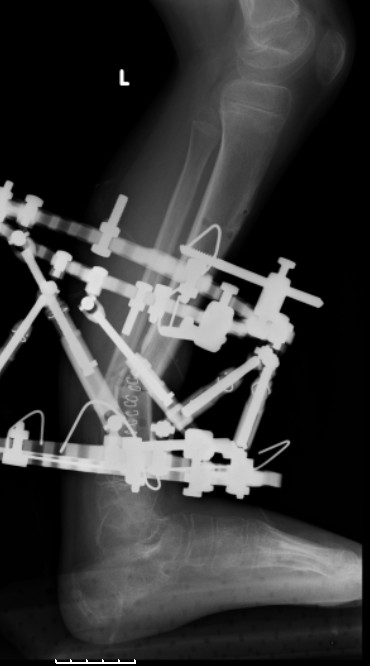

Sasha kuda delsya Lateral final snimok??

Ya poslal vse vPP presenttion.

Sasha kuda delsya Lateral final snimok?

Mark

Temporary Intentional Leg Shortening and Deformation to Facilitate Wound Closure Using the Ilizarov/Taylor Spatial Frame Shane J. Nho, MD, David L. Helfet, MD, and S. Robert Rozbruch, MD (PDF, 474 Kb)